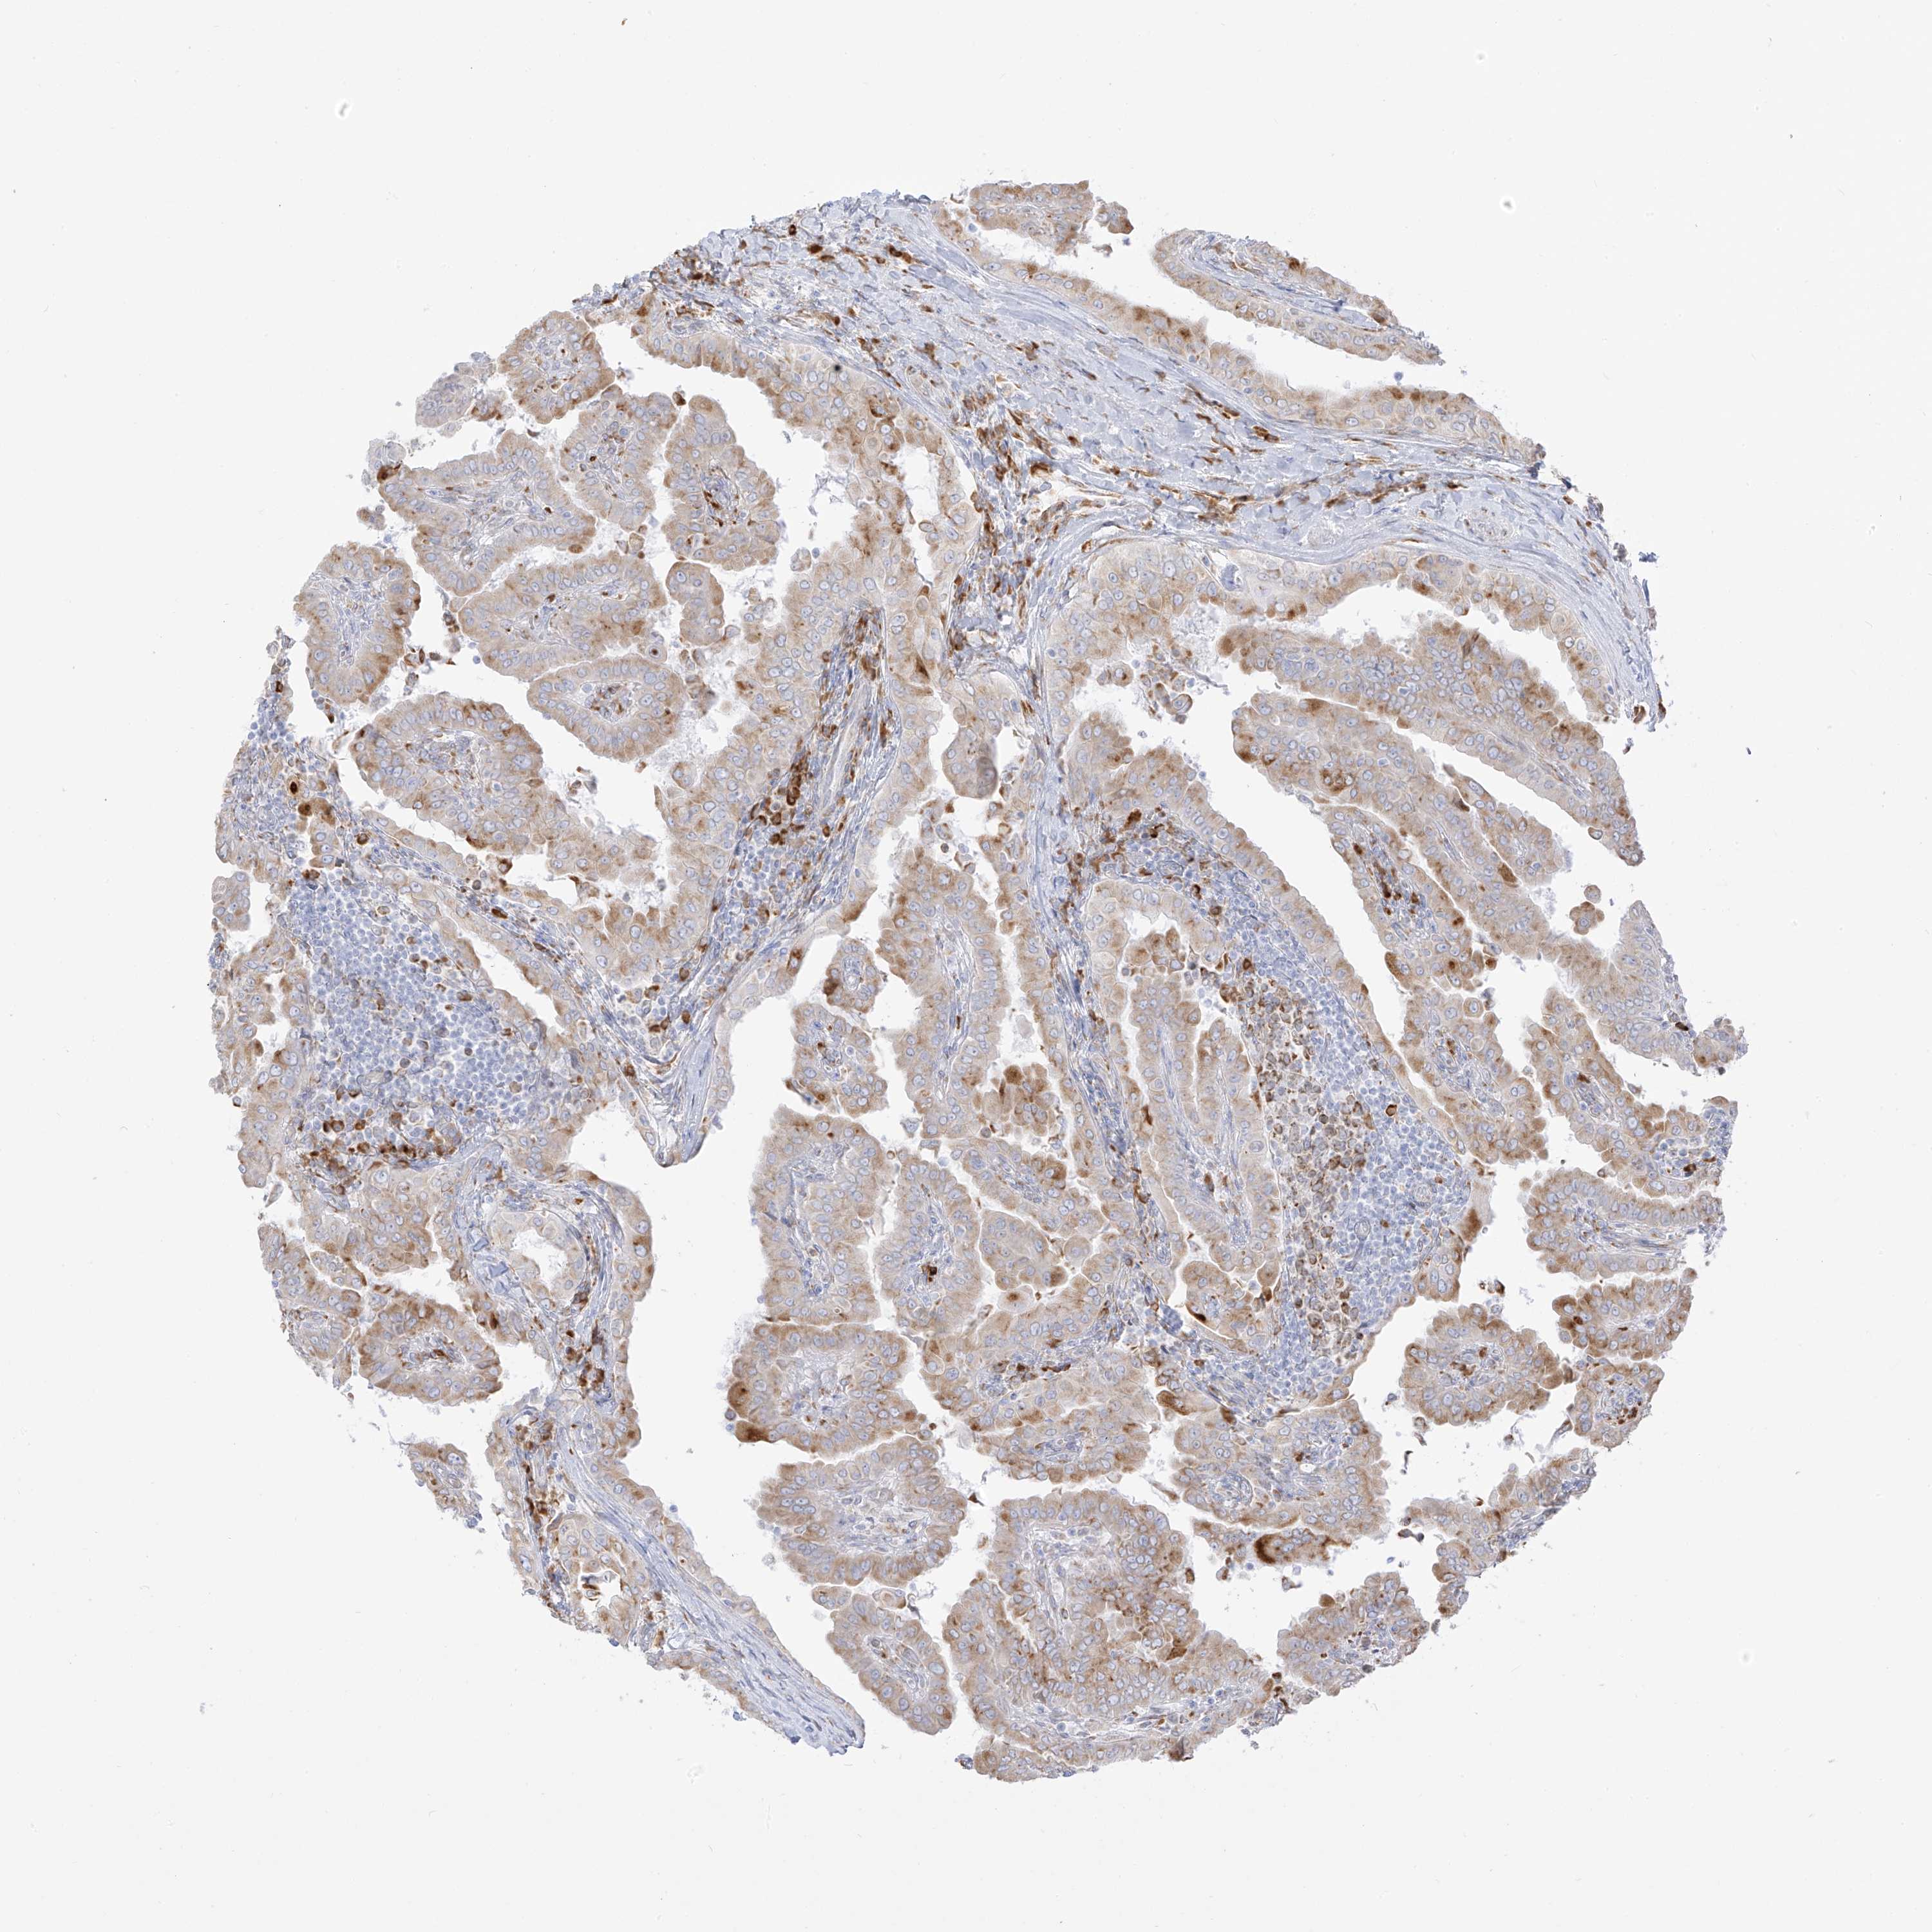

THYROID CANCER - Protein expressioni

A mouse-over function shows sample information and annotation data. Click on an image to view it in a full screen mode. Samples can be filtered based on level of antibody staining by selecting one or several of the following categories: high, medium, low and not detected. The assay and annotation is described here.

Note that samples used for immunohistochemistry by the Human Protein Atlas do not correspond to samples in the TCGA dataset.

Antibody stainingi

Antibody staining in the annotated cell types in the current human tissue is reported as not detected, low, medium, or high, based on conventional immunohistochemistry profiling in selected tissues. This score is based on the combination of the staining intensity and fraction of stained cells.

Each image is clickable and will lead to virtual microscopy that enables deeper exploration of all samples and also displays staining intensity scores, fraction scores and subcellular localization as well as patient and tissue information for each sample.

Antibody HPA030827

Antibody HPA030829

Staining

High

Medium

Low

Not detected

Intensity

Strong

Moderate

Weak

Negative

Quantity

>75%

75%-25%

<25%

None

Location

Nuclear

Cytoplasmic/membranous

Cytoplasmic/membranous,nuclear

Papillary adenocarcinoma, NOS

Follicular adenoma carcinoma, NOS